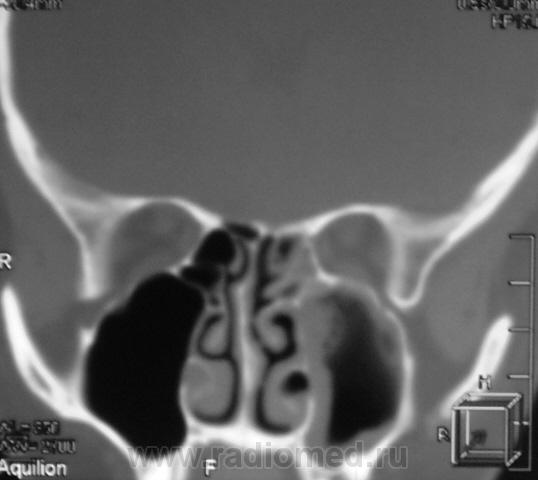

ППН.   Клиника гайморита.

Да, эксудативный левосторонний гайморит, в данной случае следует исключать одонтогенную природу, что более вероятно, вообще на данный момент на всех программных обеспечениях МСКТ, имеется мультипланарная программа с мощью которой все 2 ряда зубов как на ладони, с её помощью  удубнее оценивать состояние альвеолярных бухт, другое дело включена ли она в пакет приобреоенных программ.

Все-таки, гаймароэтмоидит: имеется содержимое в левых клетках решетчатого лабиринта. А почему одонтогенный? Зубы внедрены в пазухи с обеих сторон, оценить состояние периапикальных мягких тканей слева из-за жидкости не предсталяется возможным.

Но изменения корней зубов или пролабирование пломбировочного материала-возможно оценить, конечно не поданным сканам, а на рабочей станции, поэтому я только предпологаю, что возможно это одонтогенной природы.